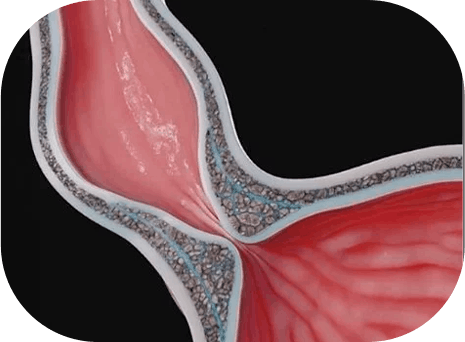

A acalasia é uma alteração da motilidade do esôfago. Em termos simples, o esôfago perde parte da capacidade de empurrar o alimento corretamente e o esfíncter na transição com o estômago não relaxa como deveria. É justamente essa falha no relaxamento que provoca o “entalo”, principalmente com alimentos sólidos.

Quando há indicação cirúrgica, um dos tratamentos mais conhecidos é a Miotomia de Heller, procedimento que reduz a pressão da musculatura na transição entre esôfago e estômago. Em outras palavras, a cirurgia “abre” essa passagem, facilitando a deglutição.

A cirurgia robótica oferece um ganho técnico importante em um procedimento delicado como esse. A principal vantagem está na precisão dos movimentos, o que ajuda o cirurgião a tratar a musculatura do esôfago com controle refinado, preservando estruturas importantes, como a mucosa.